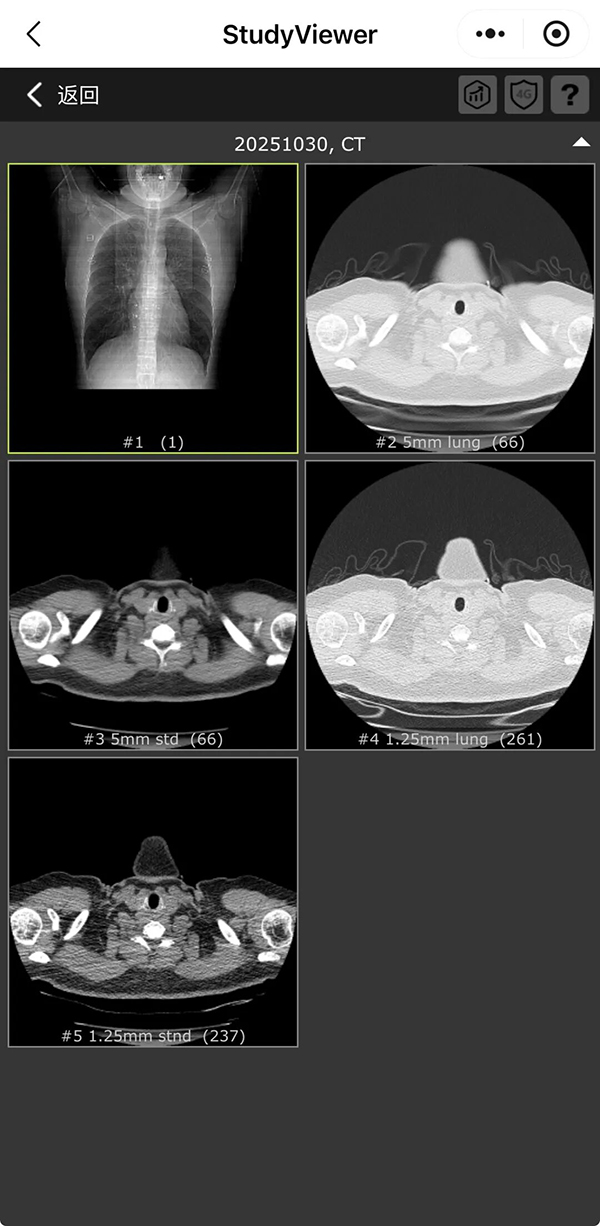

进入医疗影像检查清单界面,选择需要查看的检查,点击进入,即可查看检查报告和检查影像。